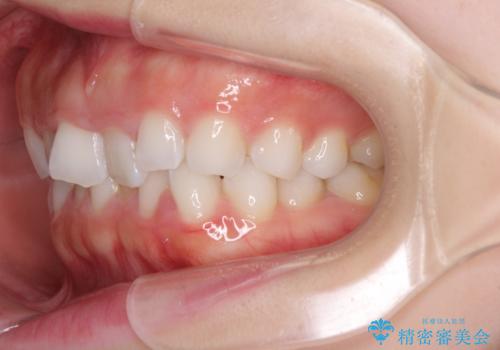

デコボコと深い咬み合わせの改善 インビザラインによる矯正治療

- 口元のデコボコと深い咬み合わせ(ディープバイト)を気にして来院された患者様です。

インビザラインによる上下歯列の拡大と、IPR(歯と歯の間を削る)にるスペースの獲得により、口元のデコボコとディープバイトを改善することとしました。

インビザラインは、装着していない時間がどれだけ短いかが、治療期間を大きく左右します。こちらの患者様は1日22時間以上、毎日欠かさず装着してくださったため、1年強という短期間で満足のいく歯列に整えることができました。